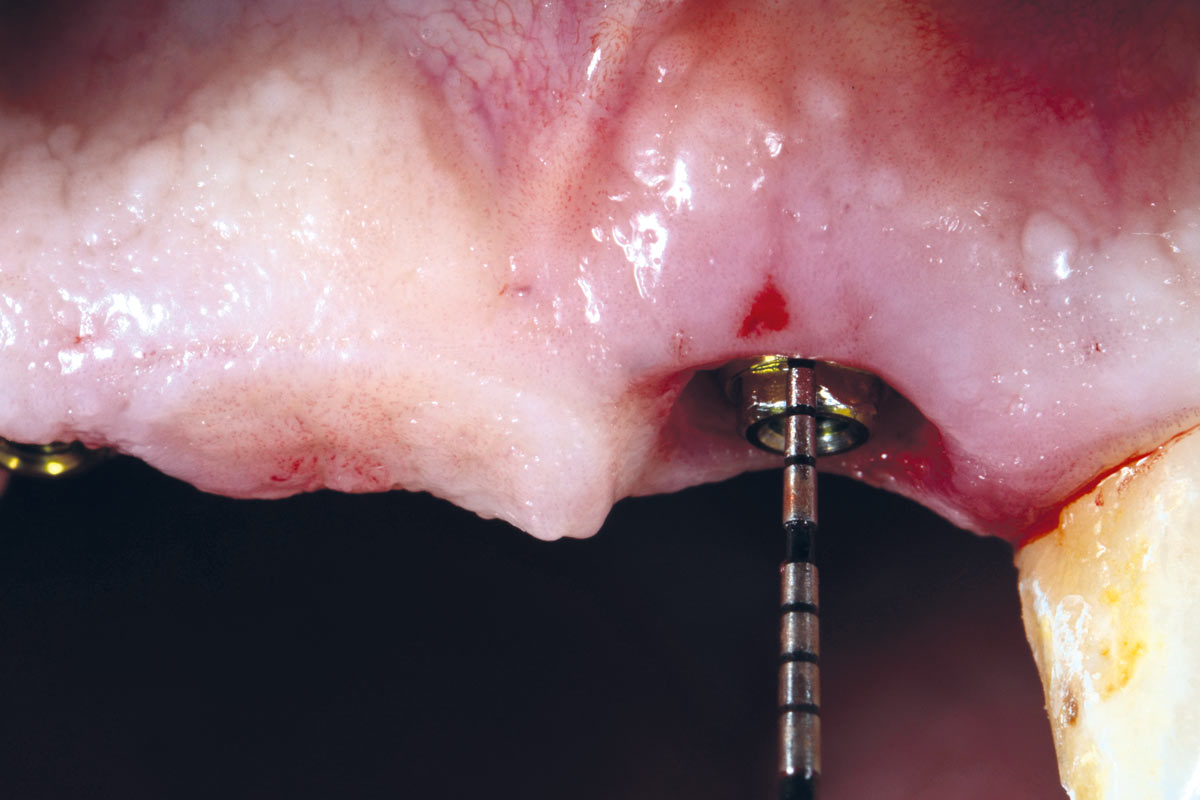

14/17 - Implant placement 6 months post-operative.

Socket preservation using cerabone® and Straumann® Emdogain® - Dr. S. Pelekanos